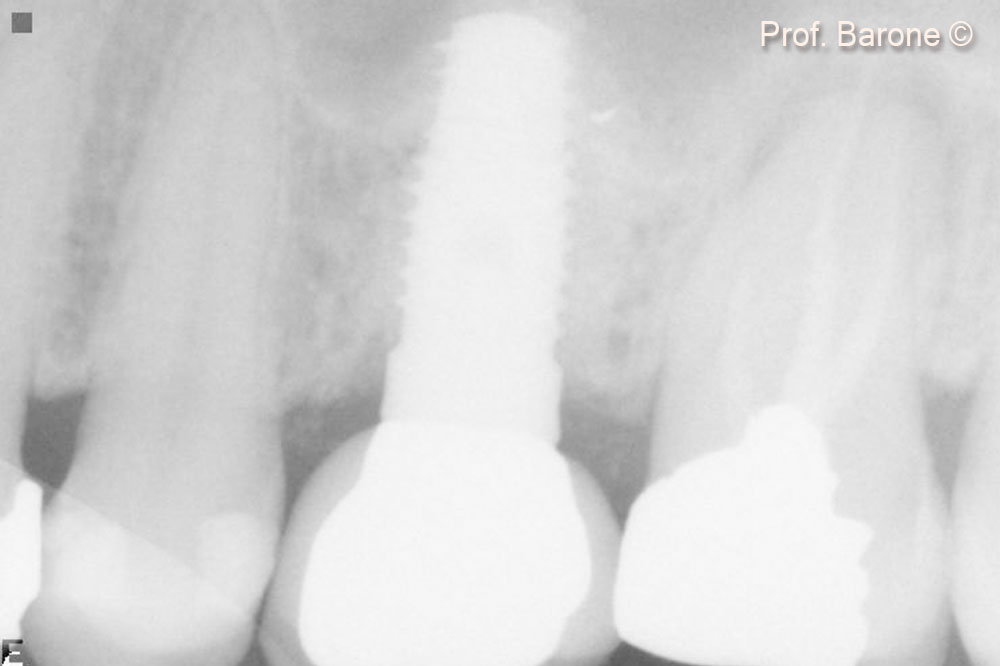

Periapical Radiograph at 3-year follow up